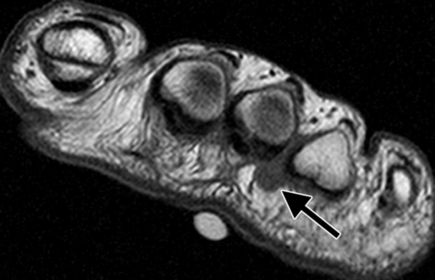

| What does the arrow show? What could this be? | Teardrop-shaped hypointense lesion in third interspace. Could be morton's neuroma |